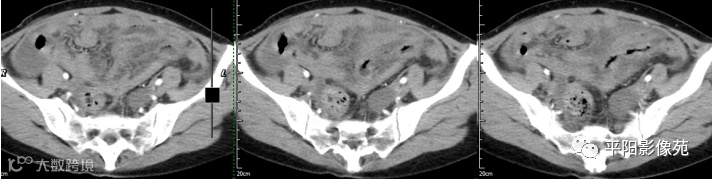

腹部增强 动脉期